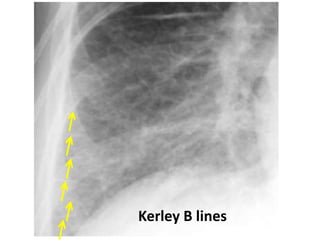

Kerley B lines